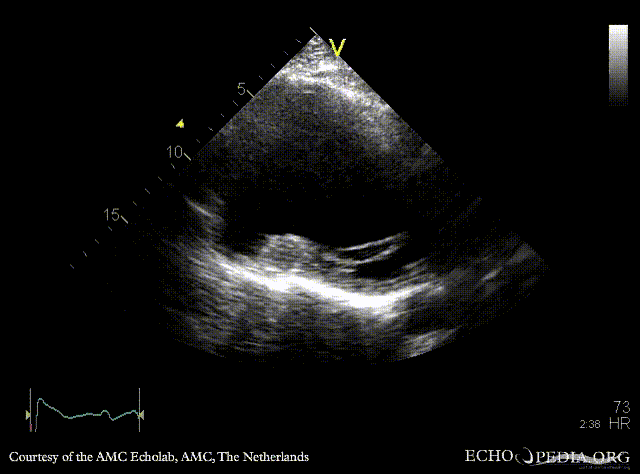

PLAX: large aneurysm of left ventricle